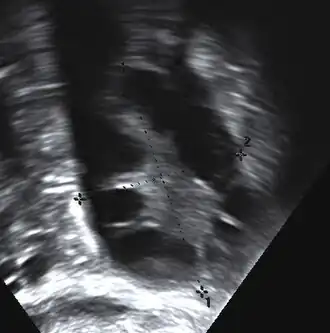

A polycystic ovary

• Polycystic ovaries: There are small cysts on one or both ovaries. Ovaries might enlarge and compress follicles surrounding the eggs. As a result, ovaries might fail to function regularly. This disease is related to the number of follicles per ovary each month, growing from the average range of 6–8 to double, triple, or more.

The syndrome acquired its most widely used name due to the common sign on ultrasound examination of multiple (poly) ovarian cysts. These "cysts" are immature ovarian follicles. The follicles have developed from primordial follicles, but this development has stopped ("arrested") at an early stage, due to the disturbed ovarian function. The follicles may be oriented along the ovarian periphery, appearing as a 'string of pearls' on ultrasound examination.[63]

Gynecologic ultrasonography first looks for small ovarian follicles.[75] To count as polycystic ovaries, at least 20 follicles need to be present, smaller than 9 mm. This used to be 12 in older diagnostic criteria.[16] A less clear marker of PCOS is enlarged ovaries.[75] Ovary need to be at least 10 cm3 to count.[16] For sexually active individuals or those that agree, a transvaginal ultrasound approach is preferred. Alternatively, AMH levels can be tested in the blood.[75] Laparoscopic examination may reveal a thickened, smooth, pearl-white outer surface of the ovary. This would usually be an incidental finding if laparoscopy were performed for some other reason, as it would not be routine to examine the ovaries in this way to confirm a diagnosis of PCOS.[78]